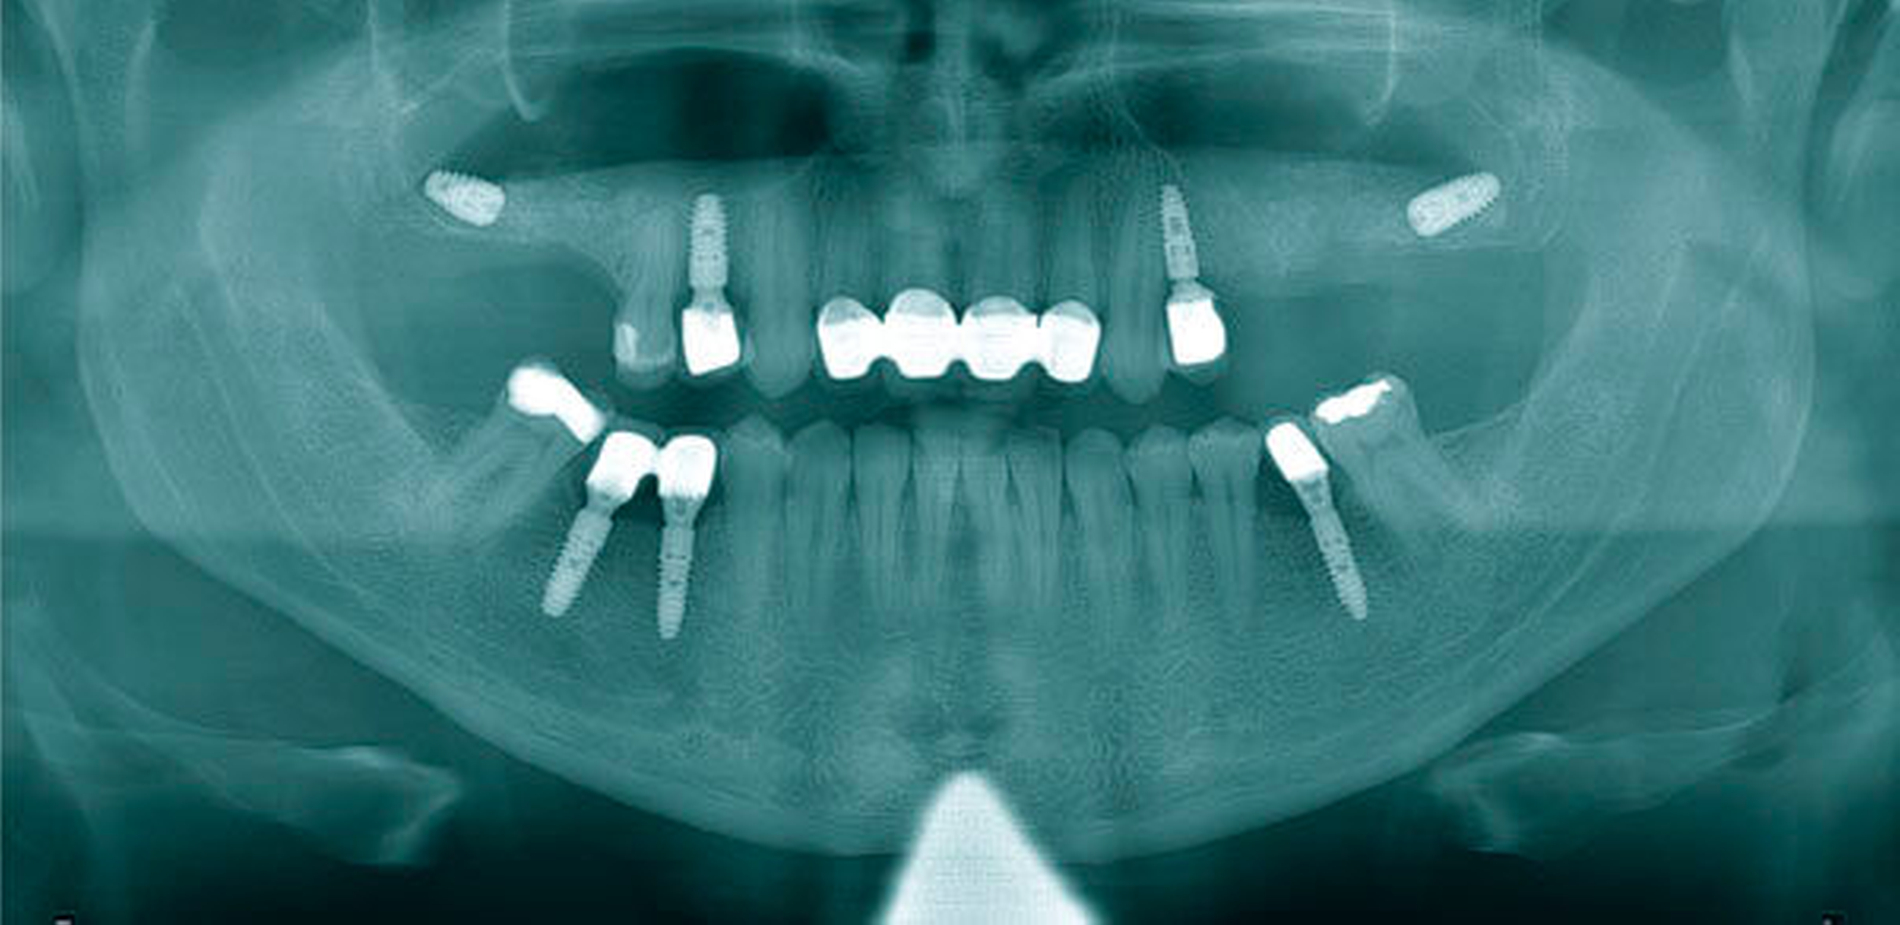

Bei der klinischen Untersuchung zeigten sich beide Kiefer totalprothetisch versorgt. Im Ober- und im Unterkiefer waren zur prothetischen Verankerung jeweils vier Implantate inseriert worden. In der durchgeführten Panoramaschichtaufnahme (PAN) zeigten sich alle Implantate osseointegriert. Zusammen mit den klinischen Befunden ergab sich kein Hinweis auf eine Periimplantitis oder einen weiteren Infektfokus. Die im Bereich des linken Sinus maxillaris nebenbefundlich festgestellte Opazität erweckte den Verdacht auf das Vorliegen eines metallenen Fremdkörpers in Form eines dentalen Implantats (Abbildung 1).

Bei der klinischen Untersuchung zeigte sich ein Druckschmerz über der linken Kieferhöhle und dem linken Sinus frontalis. In der PAN bestätigten sich eine beidseitige Augmentation der Oberkieferalveolarfortsätze von 17 bis 15 und von 25 bis 27, eine totale Verschattung der linken Kieferhöhle sowie beidseitig im Boden der Kieferhöhlen befindliche metallische Fremdkörper (Abbildung 5).